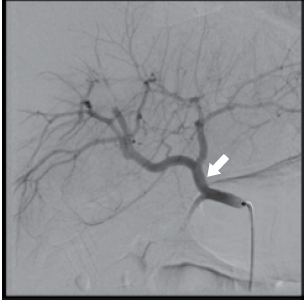

Considere a angiografia visceral apresentada e assinale a alternativa que corresponde à artéria apontada pela seta.